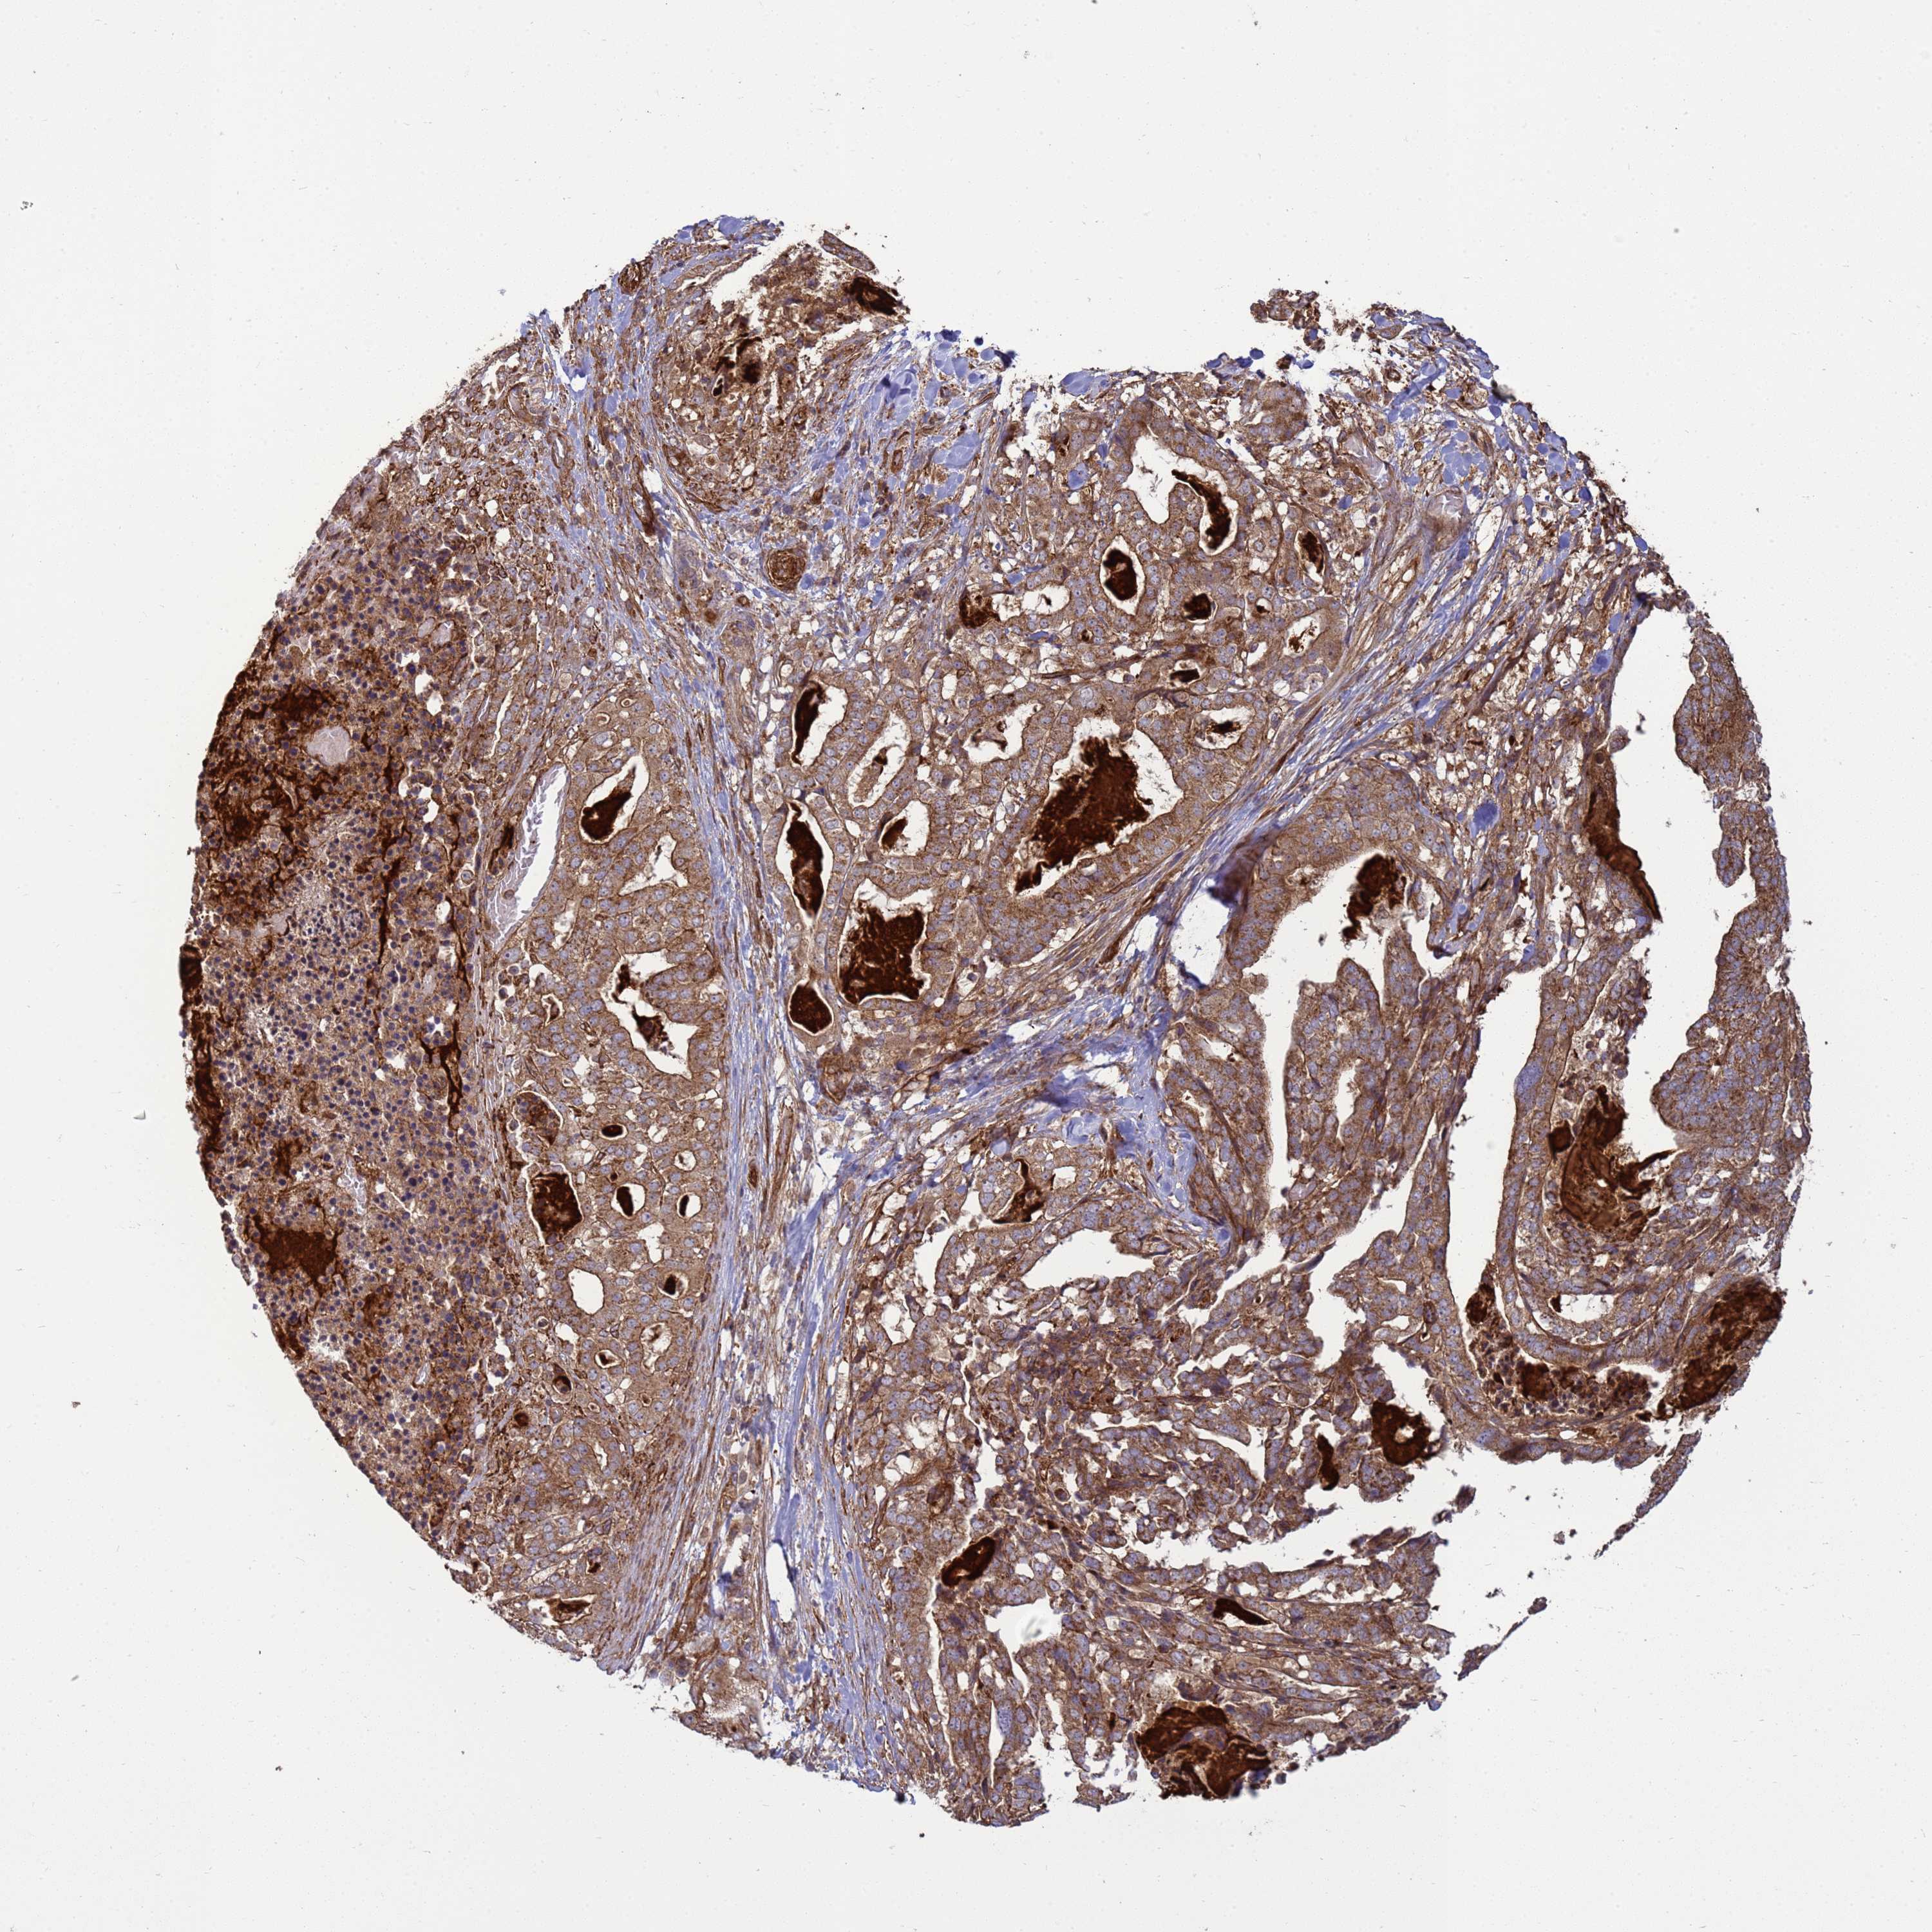

STOMACH CANCER - Protein expressioni

A mouse-over function shows sample information and annotation data. Click on an image to view it in a full screen mode. Samples can be filtered based on level of antibody staining by selecting one or several of the following categories: high, medium, low and not detected. The assay and annotation is described here.

Note that samples used for immunohistochemistry by the Human Protein Atlas do not correspond to samples in the TCGA dataset.

Antibody stainingi

Antibody staining in the annotated cell types in the current human tissue is reported as not detected, low, medium, or high, based on conventional immunohistochemistry profiling in selected tissues. This score is based on the combination of the staining intensity and fraction of stained cells.

Each image is clickable and will lead to virtual microscopy that enables deeper exploration of all samples and also displays staining intensity scores, fraction scores and subcellular localization as well as patient and tissue information for each sample.

Antibody HPA046577

Antibody HPA049664

Staining

High

Medium

Low

Not detected

Intensity

Strong

Moderate

Weak

Negative

Quantity

>75%

75%-25%

<25%

None

Location

Nuclear

Cytoplasmic/membranous

Cytoplasmic/membranous,nuclear

Adenocarcinoma, NOS

Adenocarcinoma, High grade